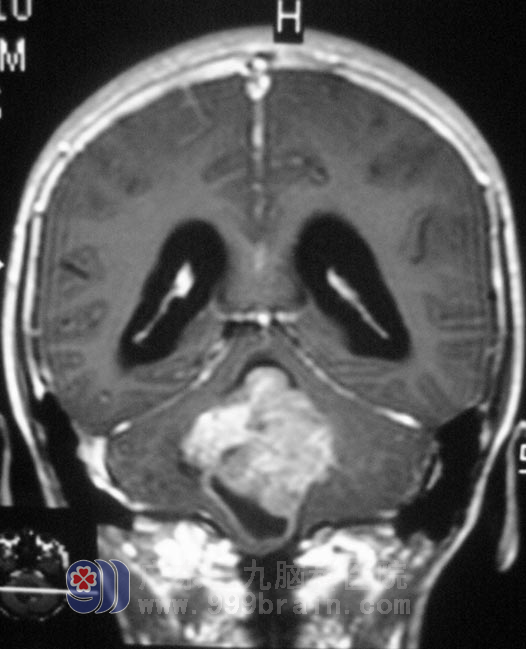

十三岁的小明,在春节后开始出现饮食不振,伴有轻微头晕、呕吐,在医院行胃肠道检查未见异常,建议调整饮食。一个月过去了,小明呕吐症状不断加重,进食量少,再次去当地医院就诊,头颅CT提示后颅窝占位,合并脑积水。小明的头痛、呕吐越来越频繁,入住广东三九脑科医院复查MR,见四脑室巨大占位,大小约3.0cm×4.0cm×5.0cm,幕上脑室扩大,梗阻性脑积水。http://www.999brain.com/

完善相关检查后,2月20日,综合神经外科 鲁明主任主刀在全麻下行四脑室占位切除术,术中显微镜下见灰白色肿瘤组织,质软,血供丰富,边界清楚,切除左侧部分扁桃体,见肿瘤与延髓交接处向上分离,边分离边切除,电凝、切开小脑蚓部约1cm,自动牵开器牵开,见灰红色肿瘤组织,伴卒中质软、血管丰富、包膜边界清晰,超声吸引器瘤内吸除部分肿瘤,止血后向上切除部分病灶后暴露四脑室顶部,向下继续分离切除肿瘤,见肿瘤与四脑室底部边界清楚,予以仔细分离切除;向左向右分离见四脑室侧孔,肿瘤分块予以切除,最后从肿瘤下方靠近延髓处切除剩余肿瘤,全切肿瘤大小约5.0cm×4.0cm×3.5cm。经过治疗后,小明头晕呕吐症状完全消失,食欲明显好转。术后病理结果为:室管膜瘤,WHO II级。